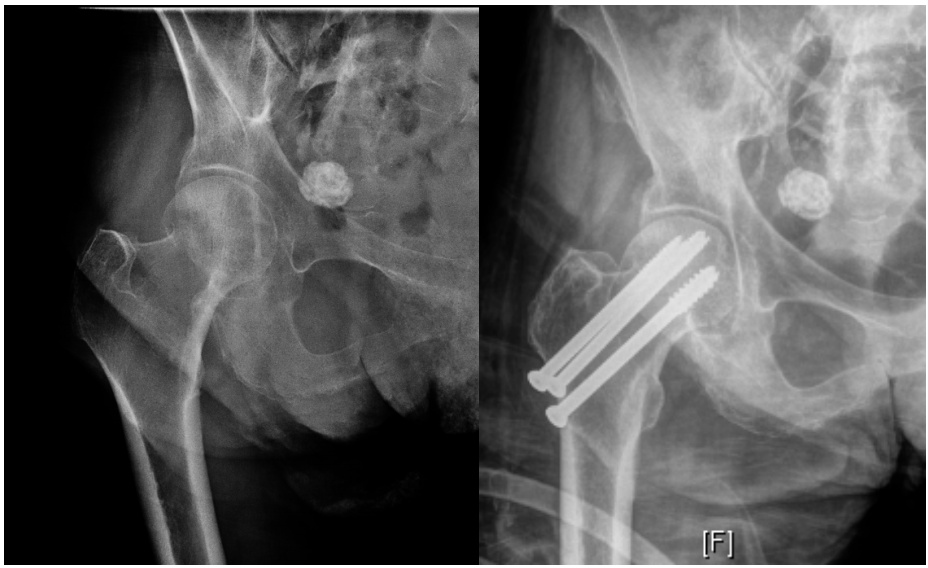

无移位股骨颈骨折:内固定与关节成形术

对于大多数患者,无移位的 Garden I 型和 II 型骨折通常采用内固定治疗(图2)。目前的固定技术主要包括空心螺钉系统和滑动髋螺钉装置。空心螺钉系统需经皮置入2-4枚螺钉跨越骨折线至股骨头;滑动髋螺钉装置则通过侧方钢板套筒内的拉力螺钉实现滑动加压。这两种技术均可微创操作,具有手术时间短、失血少、术后即刻并发症发生率低于关节成形术的优点。

图4. Garden I型骨折内固定术示例X线片(左:术前,右:术后)。